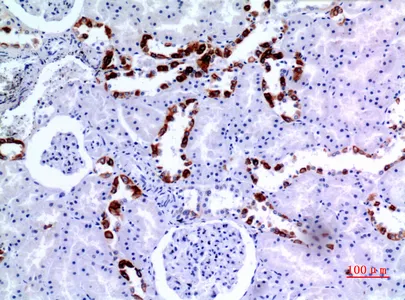

Cytokeratin 8 Rabbit Polyclonal Antibody

Cat: APRab09760

Size1:50μl Price1:$118

Size2:100μl Price2:$220

Size3:500μl Price3:$980

Size2:100μl Price2:$220

Size3:500μl Price3:$980